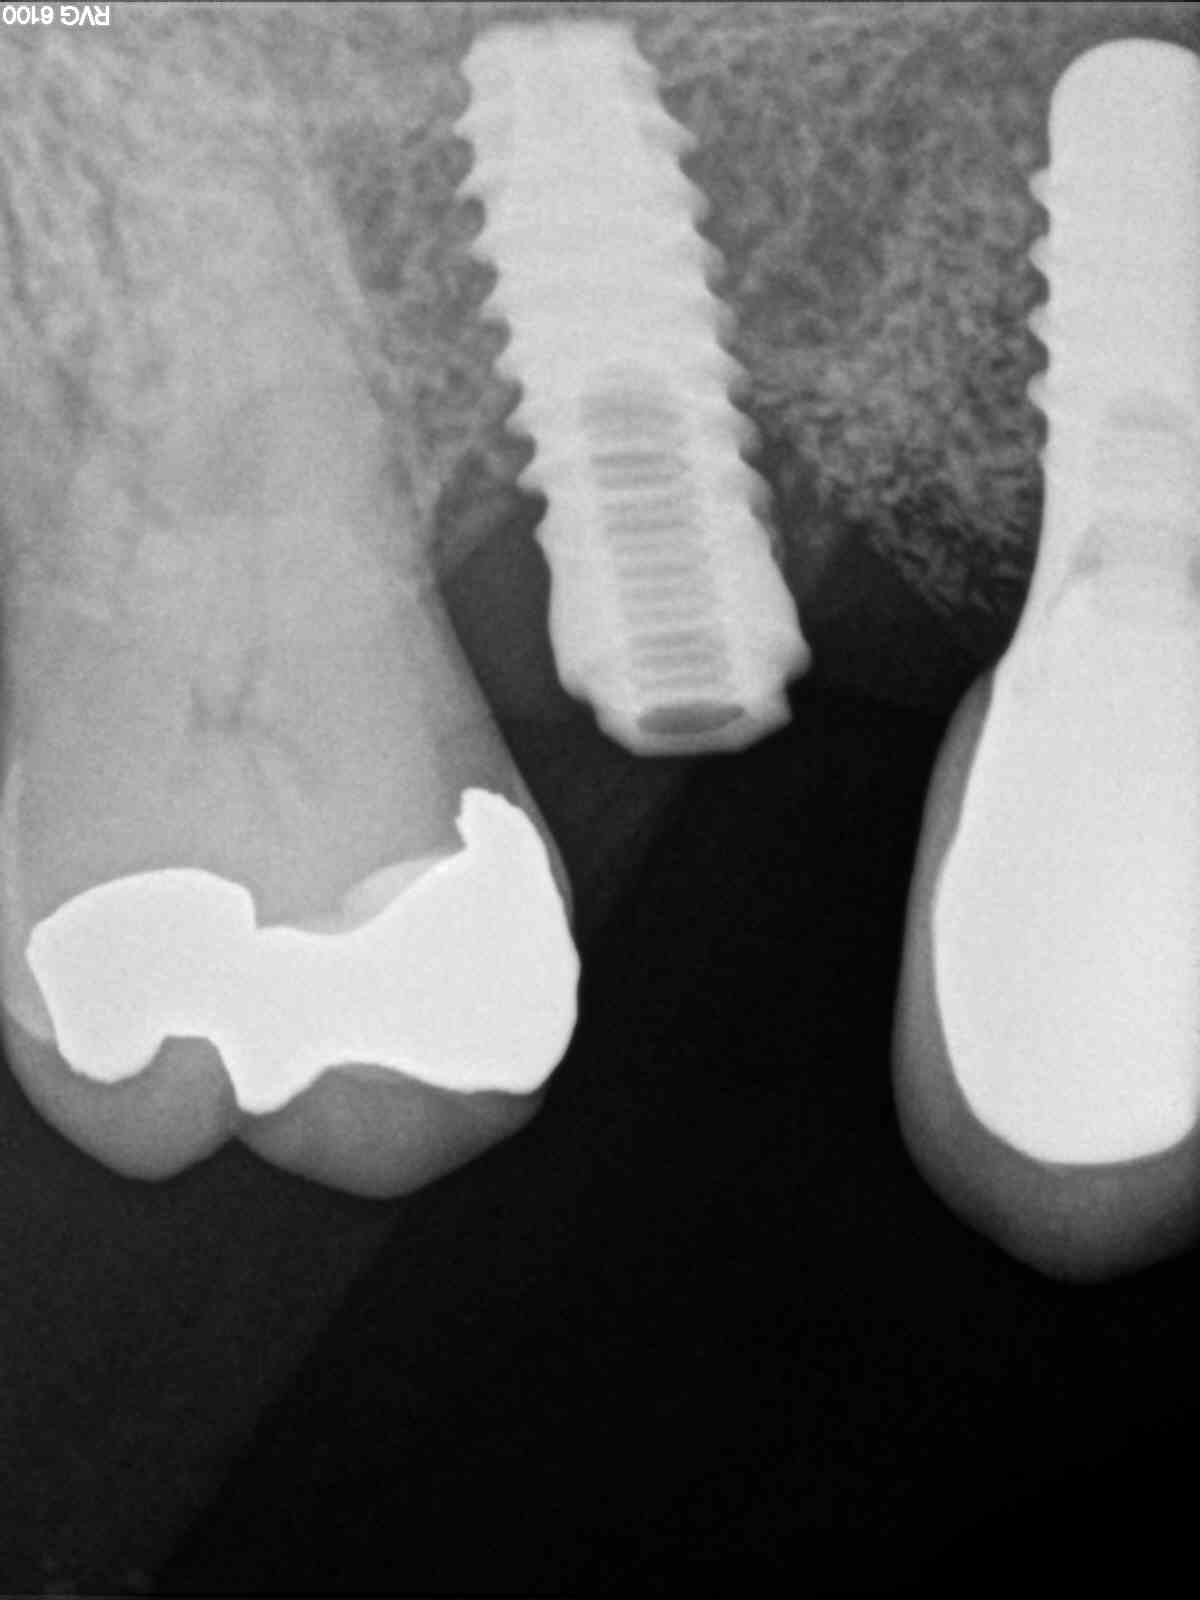

Buenos días Perdón por la calidad de las fotos He probado varios transfer y no consigo dar con el correcto ¿podríais ayudarme? Muchas gracias